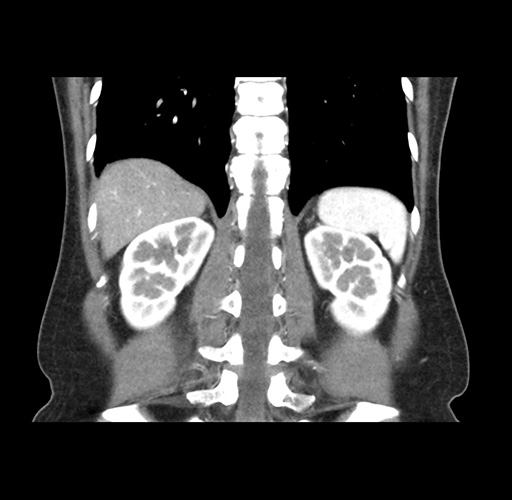

Imaging Analysis

Look through the patient's CT scan to identify any areas of concern for the necessary procedure.

Based on your CT findings, which issue(s) would give reason for "planned slowing down moment(s)" in this case?

Considering a standard left lateral sectionectomy procedure, what step(s) of the operation would you do differently in this case ?